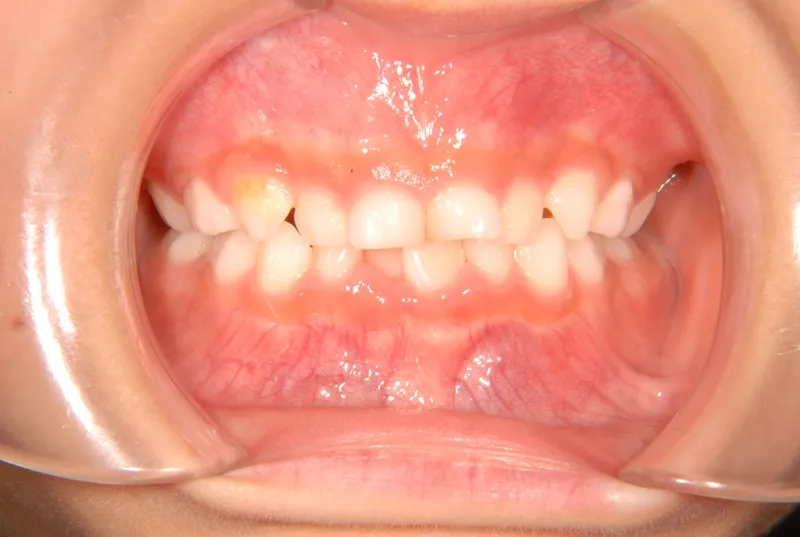

【子供の矯正(一期)】叢生・早期治療・6歳女児【S.T様】

初診時年齢 6歳まで (女性) 主訴 ガタガタ

診断名 叢生 装置名

拡大床

特徴 固い食べ物が嫌い

乳歯列が綺麗に並んでいる

ゆがんで生えている

状態 永久歯が生える隙間がない(叢生)

ガタガタ・でこぼこに生えている(叢生)

下の歯がずれて生えています。

こどもの歯は下の2本しか抜けていませんが、放っておくとガタガタがきつくなるので、早い段階からの治療としました。

初診